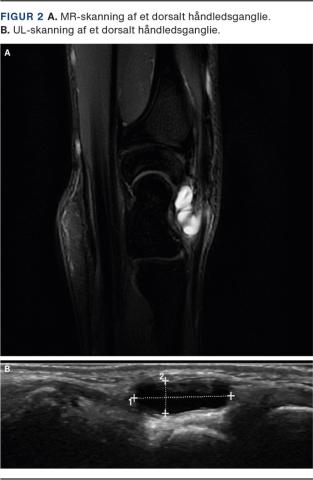

BILLEDDIAGNOSTIK

Diagnosen er primært klinisk. UL- og MR-skanning kan anvendes i tvivlstilfælde. UL-skanning er let tilgængelig og hurtig [14], og MR-skanning er bedst ved mistanke om okkulte ganglier og/eller anden intraartikulær patologi (Figur 2).